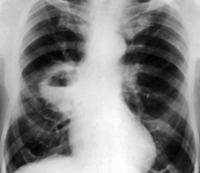

T17.8 Инородное тело в другом или нескольких отделах дыхательных путей